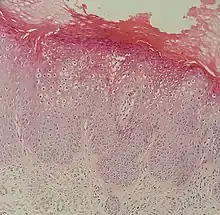

Micrograph of a flat wart

Flat warts, technically known as Verruca plana, are reddish-brown or flesh-colored, slightly raised, flat-surfaced, well-demarcated papule of 2 to 5 mm in diameter. Upon close inspection, these lesions have a surface that is "finely verrucous".[1][2] Most often, these lesions affect the hands, legs, or face, and a linear arrangement is not uncommon.[2] At histopathology, flat warts have cells with prominent perinuclear vacuolization around pyknotic, basophilic, centrally located nuclei that may be located in the granular layer.[3] These are referred to as "owl's eye cells."[3]